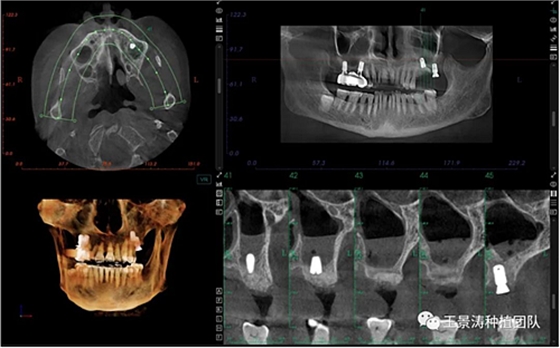

左側(cè)下頜第二磨牙及右側(cè)下頜第一磨牙同時(shí)即刻種植病例?;颊吣贻p女性,無系統(tǒng)性疾病。37及46殘冠及殘根,且46劈裂,無法冠修復(fù),必須拔除。37根尖慢性炎癥,大量肉芽組織存在,46根分叉較高,根分叉骨質(zhì)尚可。CBCT示:根尖骨質(zhì)至下牙槽神經(jīng)管距離可滿足種植體的初期穩(wěn)定性,遂考慮即刻種植,并在種植體周邊填入骨粉并覆蓋骨膜,雙側(cè)的種植體初期穩(wěn)定性相差無幾,但考慮到37根尖慢性炎癥較大,遂給予埋入式種植。